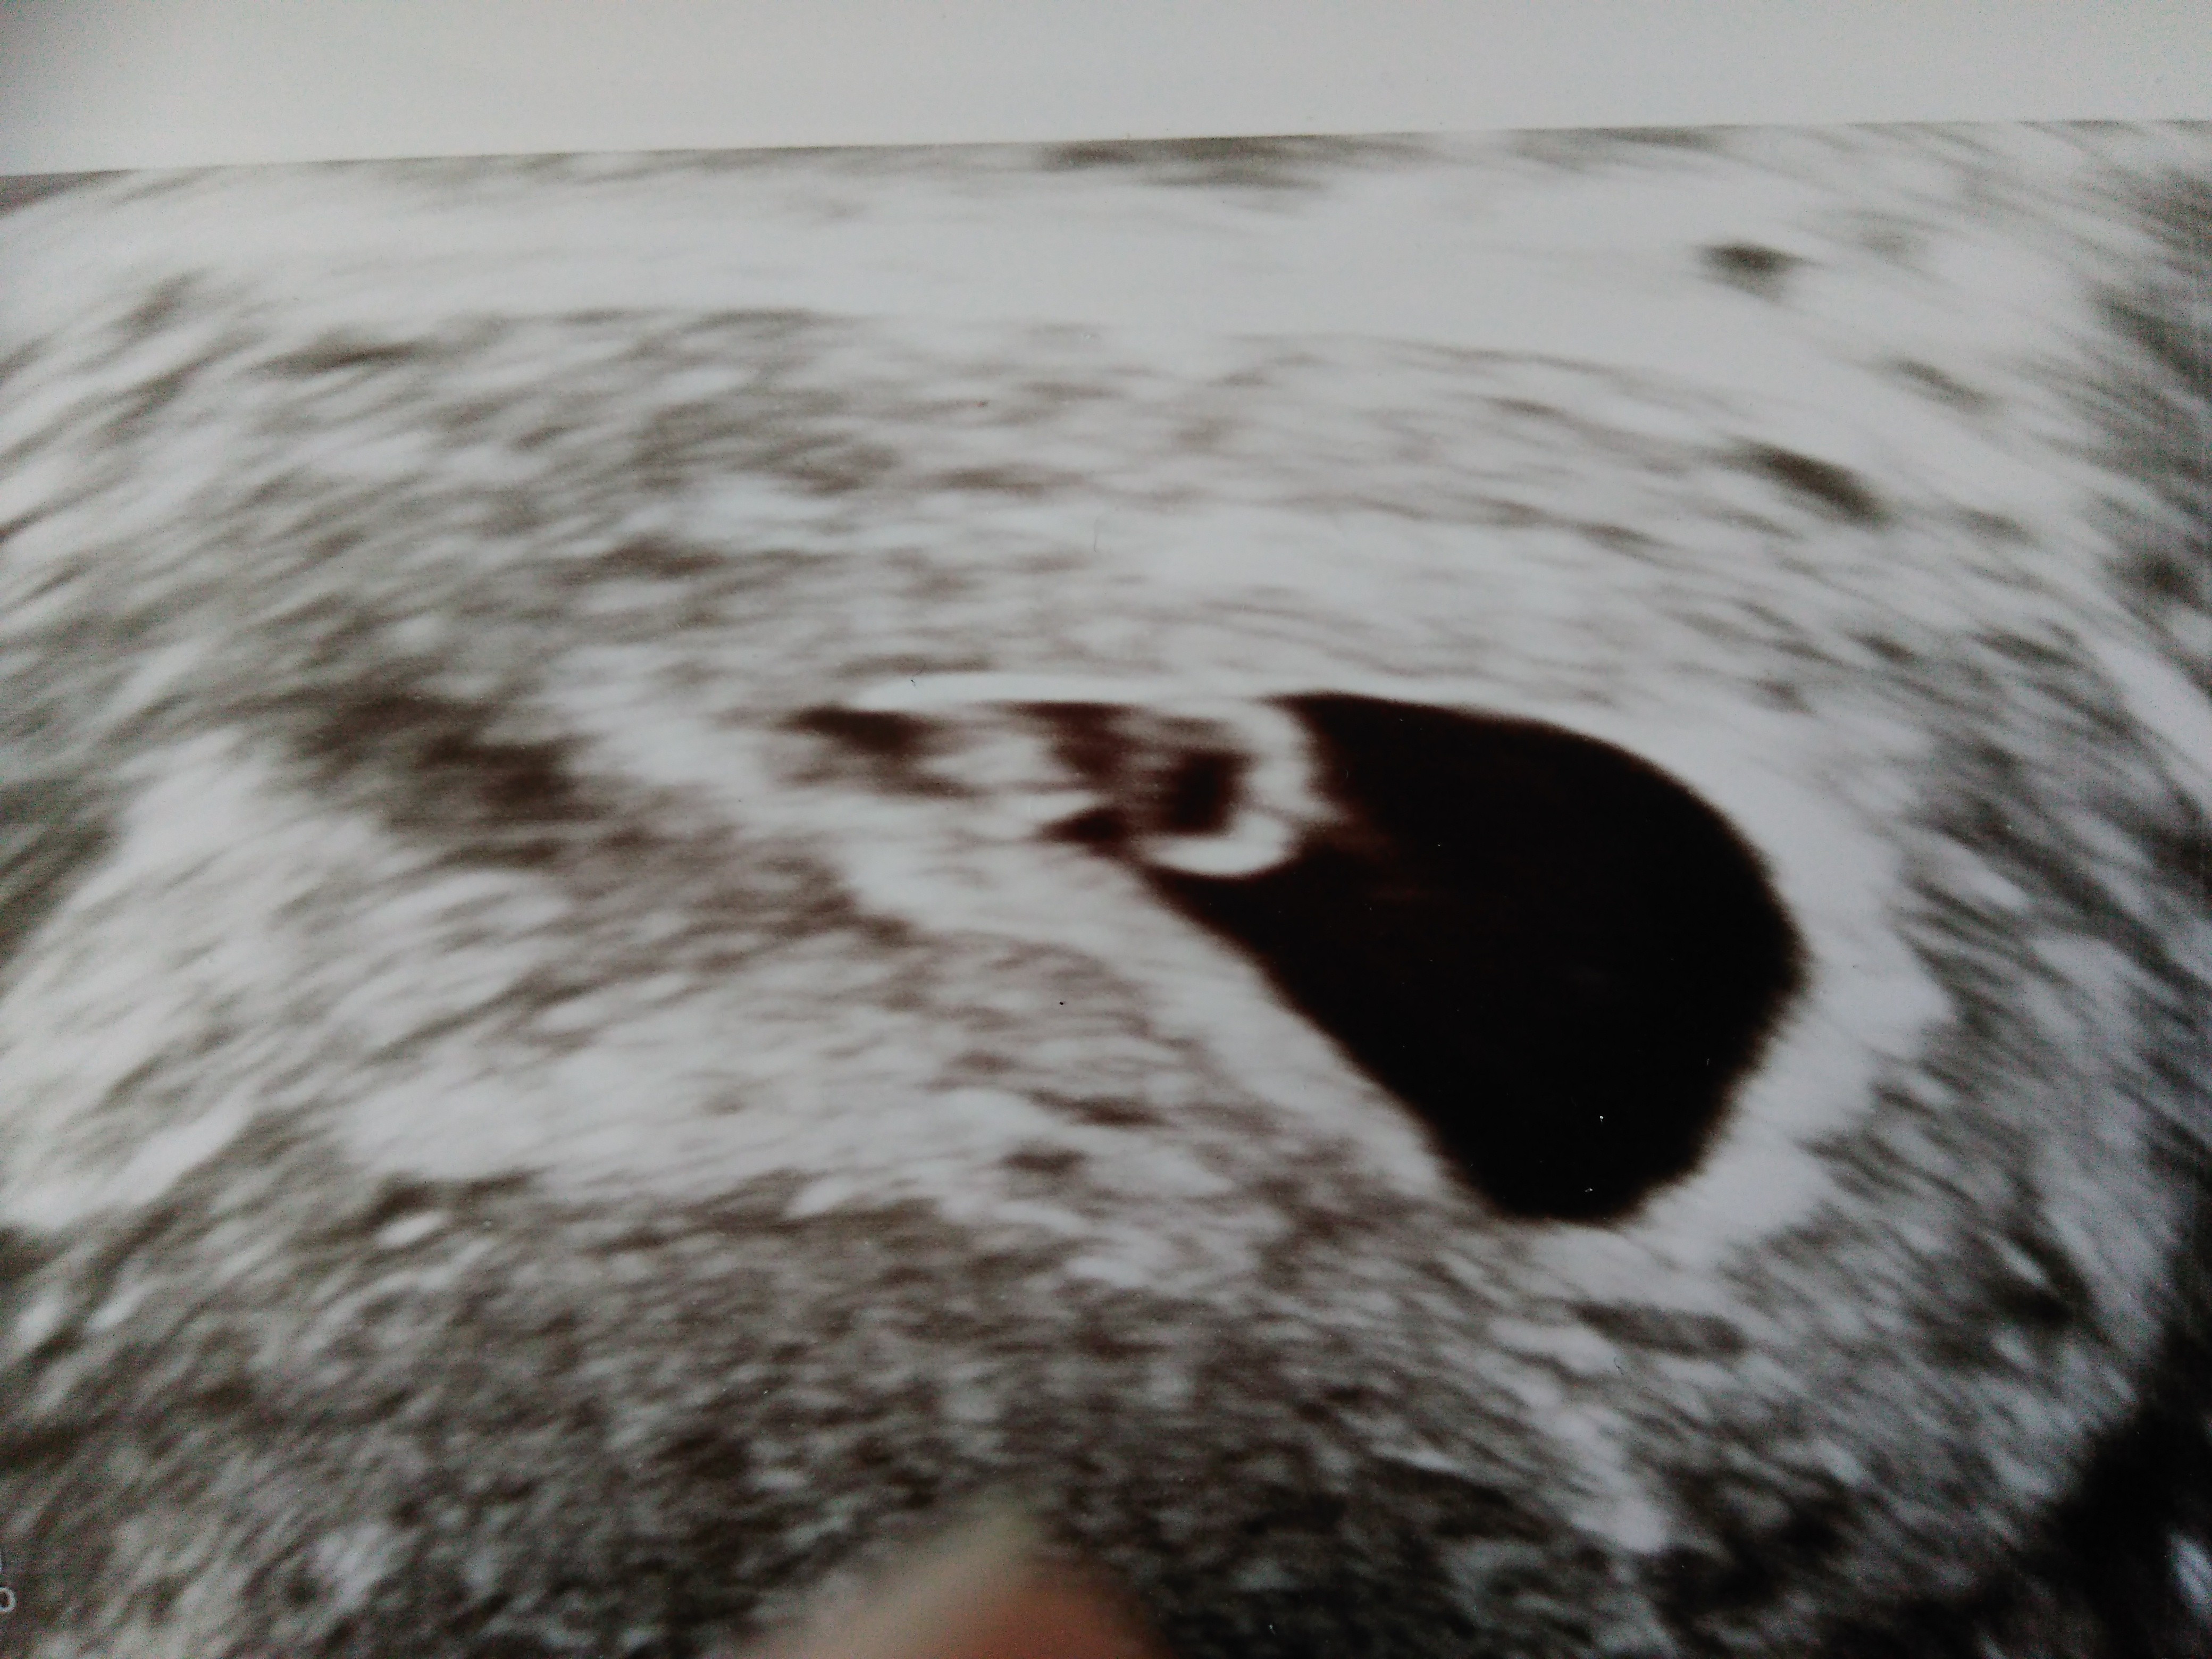

Cudownie! Bardzo się cieszę [emoji173][emoji173][emoji173]Zobacz załącznik 1094765

Nasze szczęście ma 6 mm i słyszałam serduszko i wyłam jak bóbr [emoji3590][emoji3590][emoji3590][emoji3590][emoji3590]